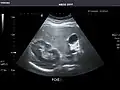

Liver

In patients with deranged liver function tests, ultrasound may show increased liver size (hepatomegaly), increased reflectiveness (which might, for example, indicate cholestasis), gallbladder or bile duct diseases, or a tumor in the liver.

Ultrasonography of liver tumors involves two stages: detection and characterization. Tumor detection is based on the performance of the method and should include morphometric information (three axes dimensions, volume) and topographic information (number, location specifying liver segment and lobe/lobes). The specification of these data is important for staging liver tumors and prognosis. Tumor characterization is a complex process based on a sum of criteria leading towards tumor nature definition. Often, other diagnostic procedures, especially interventional ones, are no longer necessary. Tumor characterization using the ultrasound method will be based on the following elements: consistency (solid, liquid, mixed), echogenicity, structure appearance (homogeneous or heterogeneous), delineation from adjacent liver parenchyma (capsular, imprecise), elasticity, posterior acoustic enhancement effect, the relation with neighboring organs or structures (displacement, invasion), vasculature (presence and characteristics on Doppler ultrasonography and contrast-enhanced ultrasound (CEUS).